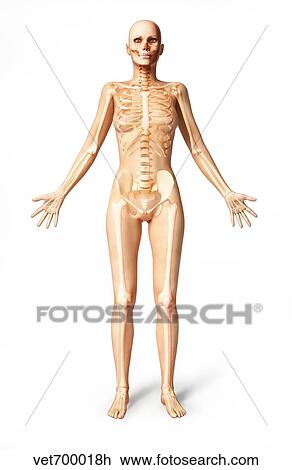

Female Standing With Skeletal Bones Superimposed Front

Female Standing With Skeletal Bones Superimposed Front